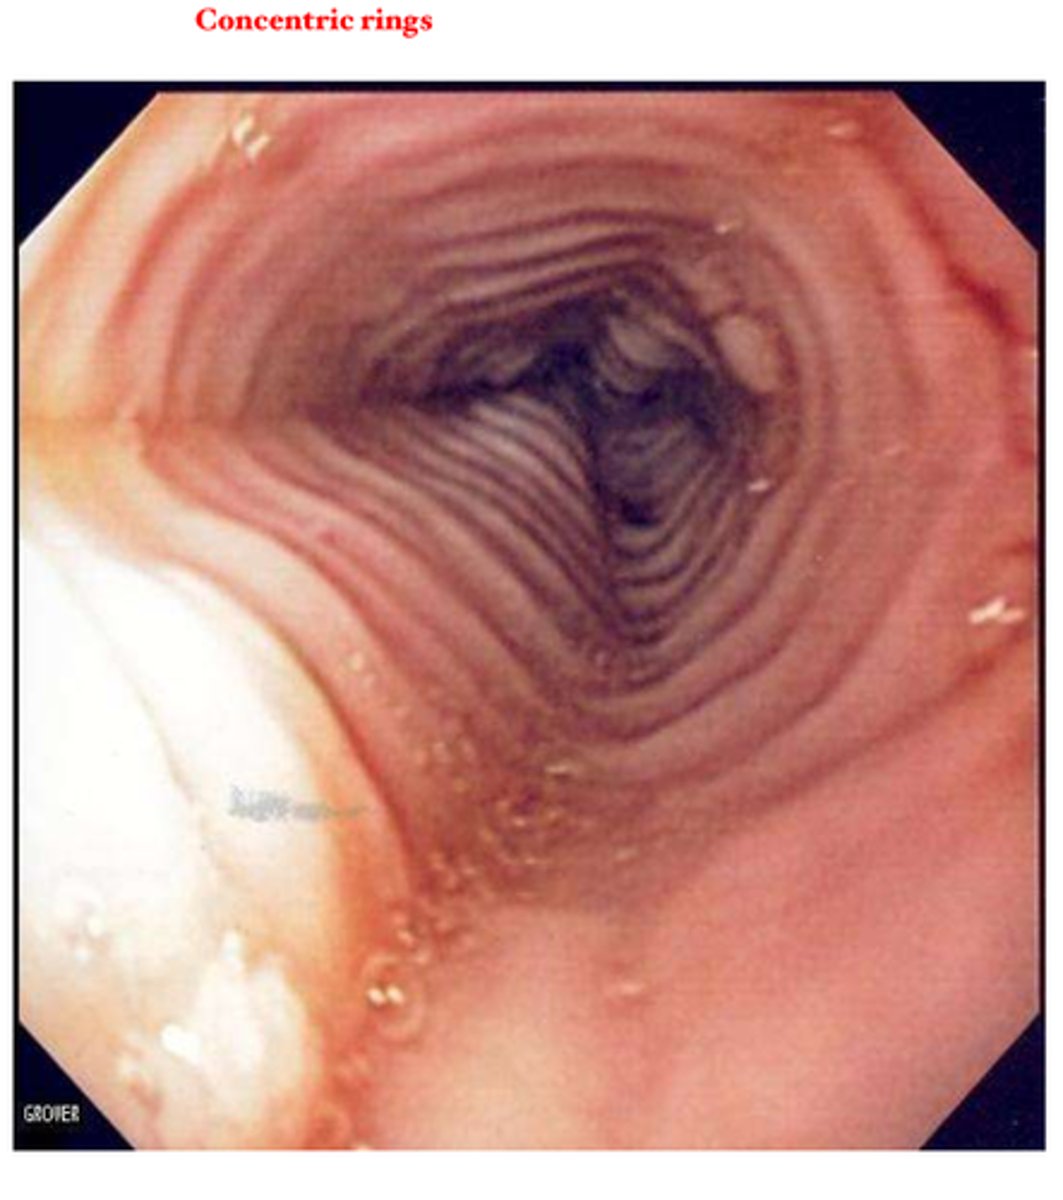

Jeremy a 34 year old male has seasonal allergies. His current complaint is dysphagia of solid foods, heartburn, and chest pain.

What test do you order to confirm your suspected diagnosis?

What do you find?

What are some labs you could order?

Hint - You conduct a barium swallow and find small-caliber esophagus, tapered strictures, or concentric rings.

1.) Endoscopy with biopsy

2.) Edema, concentric rings, exudates, furrows, and strictures

3.) CBC to determine if eosinophils are elevated. Allergen specific IgE test.

Jeremy has esinophilic esophagitis

How do you treat eosinophilic esophagitis?